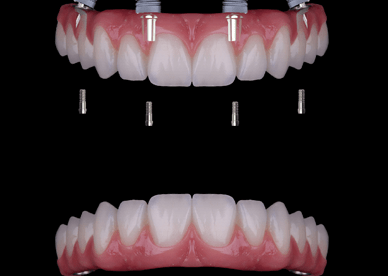

Implantes dentales en Madrid – calidad y precio en Barrio Salamanca En Dr. Alejandro Prieto Dental Clínica Dental, tu clínica dental de confianza en el Barrio Salamanca de Madrid, somos expertos en implantes dentales de todos los tipos. Mezclamos implantología avanzada con alta estética. Si estás buscando una solución duradera, estética y con precios competitivos, […]